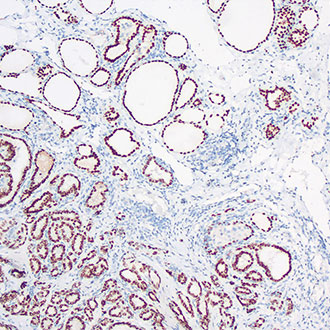

IHC

免疫组织化学(IHC)